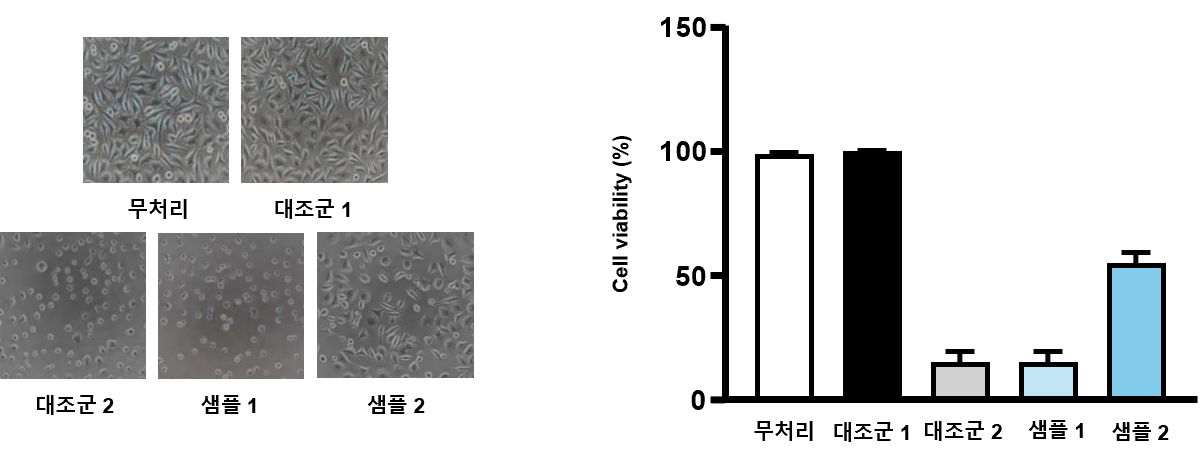

결과 예시

시험물질 증식포화 상태

(Confluent monolayer)

원형세포 비율

(Percent Rounding)

세포질내 과립을 포함하지 않은 세포의 비율

(Percent Cell without Intracytoplasmic Granules)

용해도

(Percent Lysis)

등급

(grade)

반응

(Reactivity)

무처리 (+) 0 0 0 0 None

대조군 1 (+) 0 0 0 0 None

대조군 2 (-) 99 99 99 4 Severe

샘플 1 (-) 99 99 99 4 Severe

샘플 2 (-) 40 50 54 2 Mild

의료기기 세포독성 서비스 결과예시